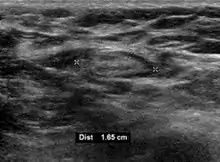

Medical ultrasonography of a typical normal lymph node: smooth, gently lobulated oval with a hypoechoic cortex measuring less than 3 cm in thickness with a central echogenic hilum.[25]

On ultrasound, B-mode imaging depicts lymph node morphology, whilst power Doppler can assess the vascular pattern.[27] B-mode imaging features that can distinguish metastasis and lymphoma include size, shape, calcification, loss of hilar architecture, as well as intranodal necrosis.[27] Soft tissue edema and nodal matting on B-mode imaging suggests tuberculous cervical lymphadenitis or previous radiation therapy.[27] Serial monitoring of nodal size and vascularity are useful in assessing treatment response.[27]

Lymphadenopathy of the axillary lymph nodes can be defined as solid nodes measuring more than 15 mm without fatty hilum.[35] Axillary lymph nodes may be normal up to 30 mm if consisting largely of fat.[35]